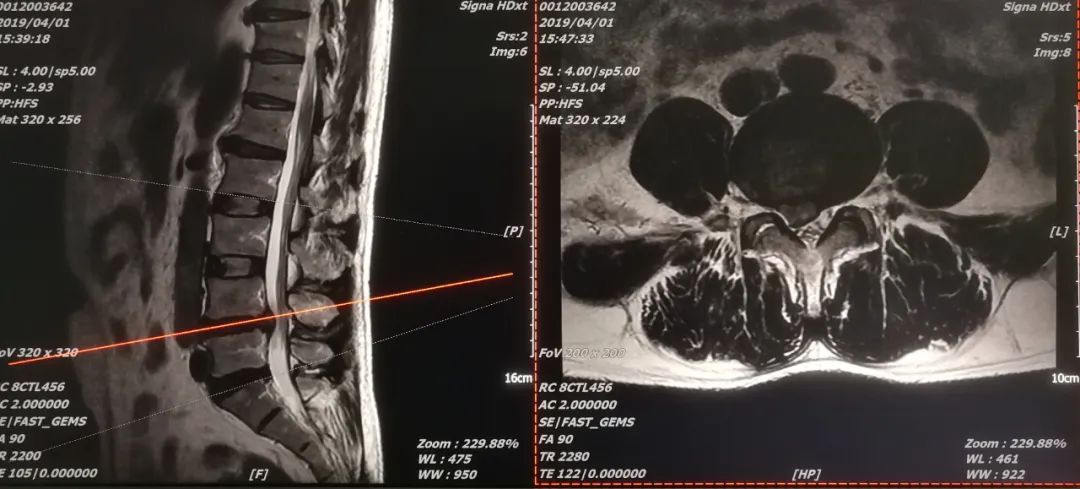

患者张某,女,60岁,因反复腰痛3年余,加重伴下肢麻痛跛行3天而入院,患者长期因腰椎间盘突出症反复发作而困扰,不时在当地诊所敷草药治疗,且皮肤因长期敷用草药致溃烂,遂就诊于我院。脊柱外科专家结合腰椎CT、MR、X线等相关检查结果,诊断为腰4/5椎间盘突出症。经保守治疗,效果欠佳。陈子华主任组织科室团队对病例进行讨论,患者具有手术指征。由于患者腰背部皮肤破损,若经后路切开椎间盘椎间融合有可能导致切口感染,经综合考虑后,决定对该患者实施微创椎间孔镜下椎间盘突出症摘除术。

征得患者及家属同意,于4月22日,科室专家团队为该患者在局麻下实施微创椎间孔镜下腰4/5椎间盘突出摘除、神经根松解术。术后患者感觉腰腿疼症状明显改善,下肢抬高自如,取得满意效果。经腰椎MR复查,突出椎间盘组织完全摘除,目前患者已康复出院。